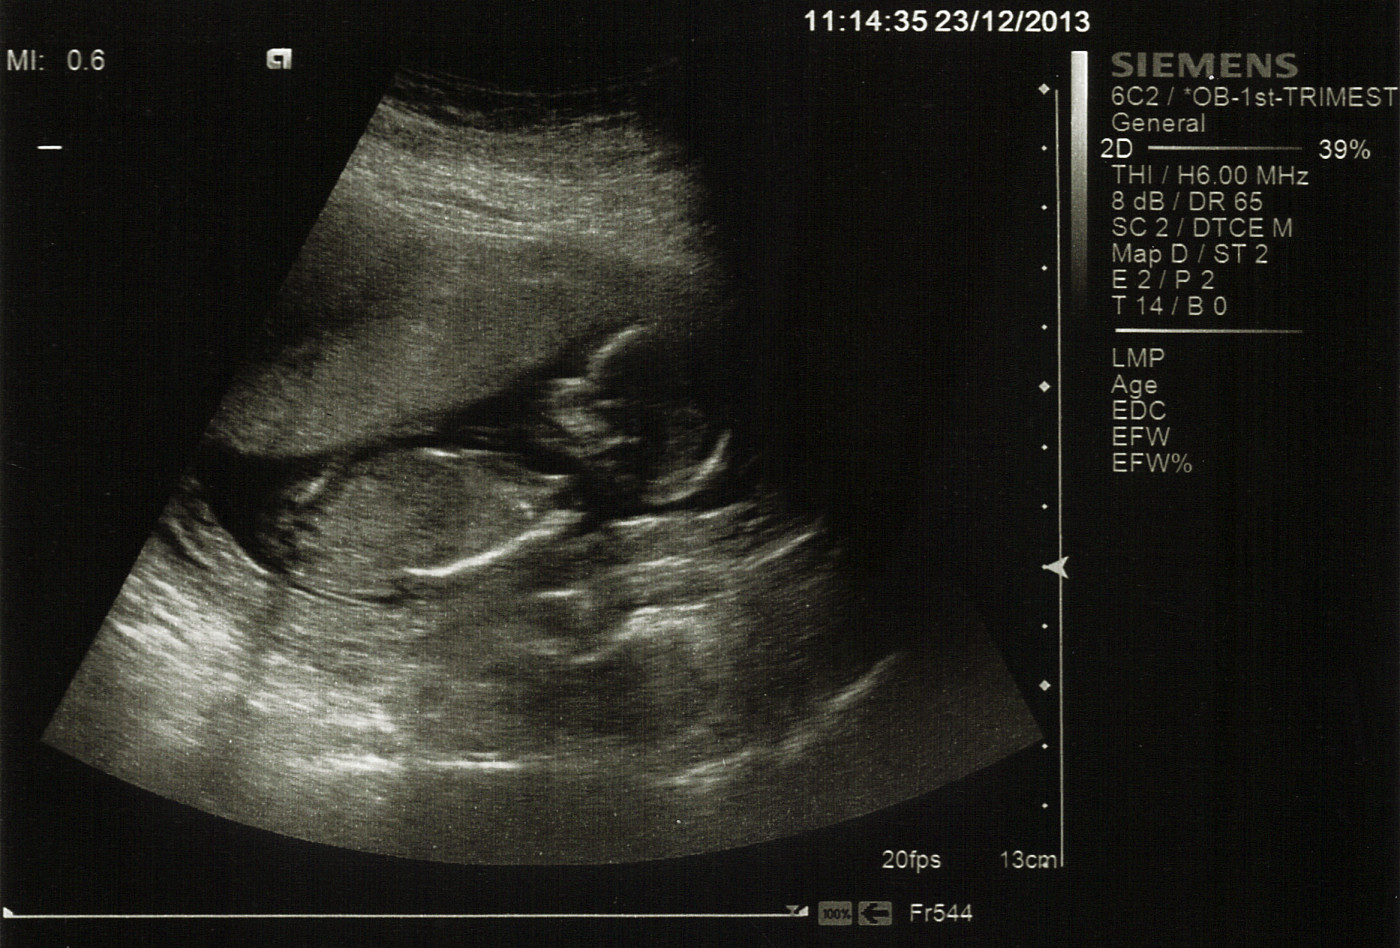

Also for those who know their stuff: there are lines underneath baby's back in the last picture that DH and I are trying to figure out what they are. Any clues?

Attachment 15865